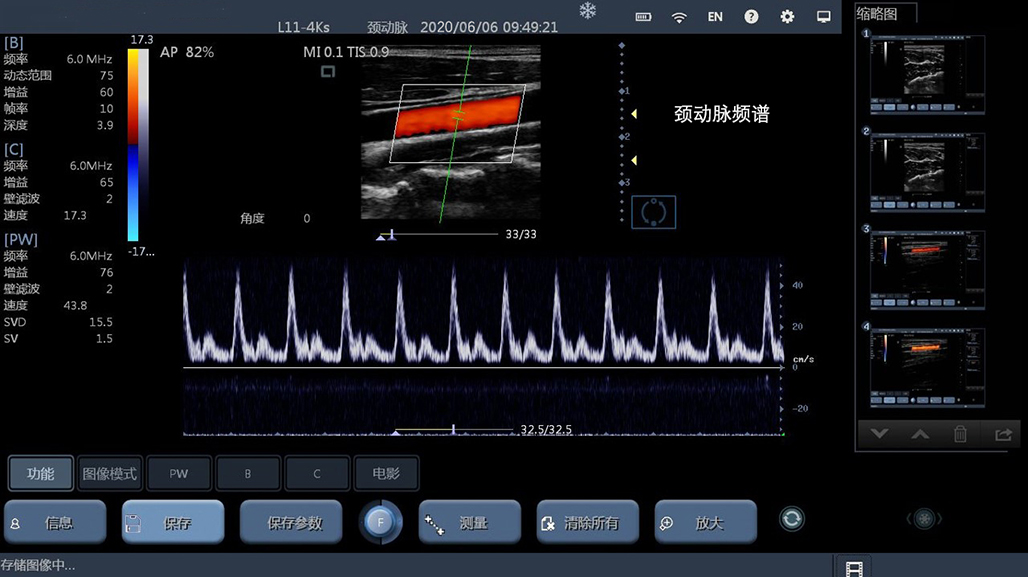

• 线阵

血管